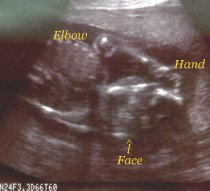

This is my hand up by my face.

Still up by my face.